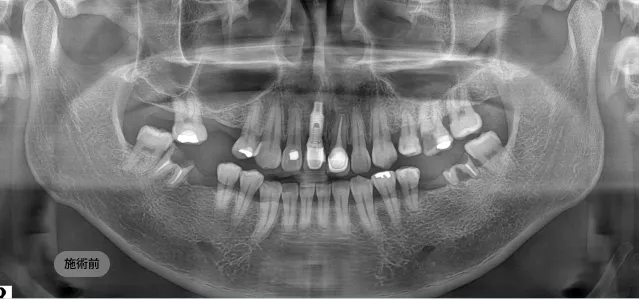

画面をドラッグして前/後を比較してみてください

長く、健康に使えるインプラントのために ブランシュ歯科は施術より「設計」を先に考えます。

精密CT、3Dシミュレーションで 正確な骨の状態を分析します。

精密診断